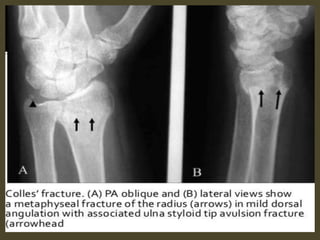

distal radius/ulnar fractures with shortening (e.g. impaction) &

angulation